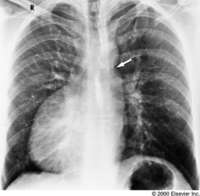

The above chest X-ray is not reversed, that is a patient with dextrocardia.

All of the heart chambers and great vessels are reversed, as seen above.

Left Ventricle (LV), Right Ventricle (RV), Left Atrium (LA), Right Atrium (RA), Pulmonary Artery (PA), Aorta (Ao).